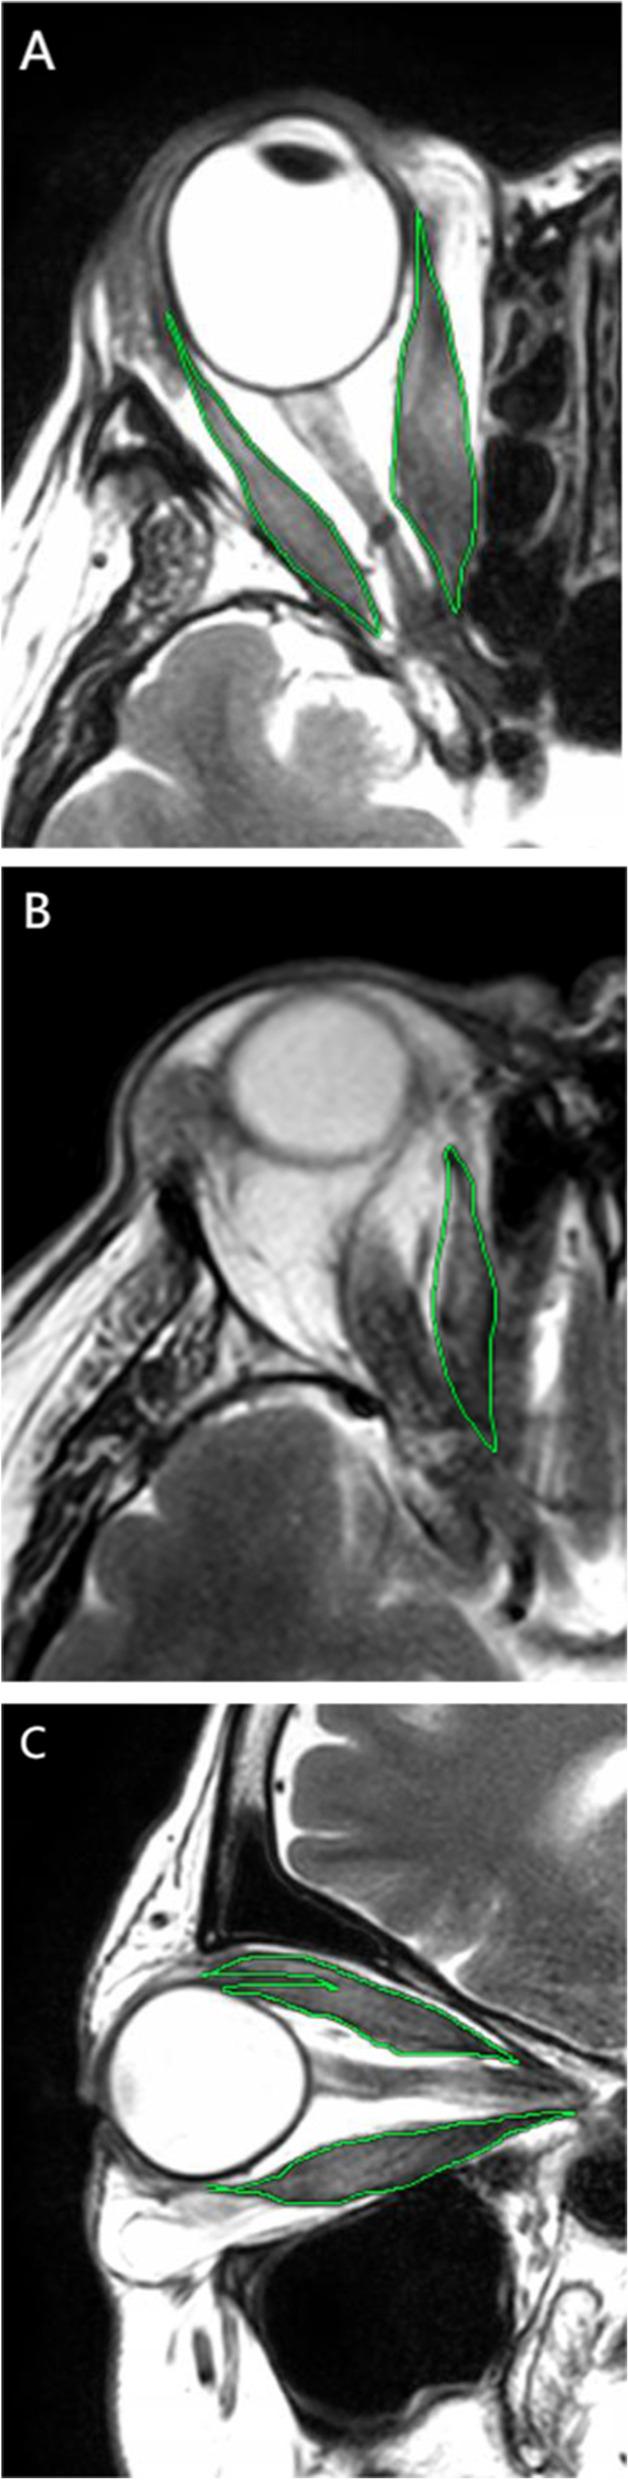

Thirty-six patients (72 orbits) with inactive TAO (43 orbits, Clinical Activity Score [CAS] < 3) or active TAO (29 orbits, CAS ≥3) were investigated retrospectively. All patients underwent ophthalmic evaluation and orbital magnetic resonance imaging. The severity of LGP and proptosis and the extraocular muscle (EOM) volume were measured. LGP and related factors were assessed by correlational and linear regression analyses. The value of LGP for discriminating the activity of TAO was evaluated by receiver-operating characteristic curve analysis.

The mean LGP was significantly higher in the active TAO group than in the inactive TAO group (P < 0.001). There were significant positive correlations between LGP severity and the CAS (r = 0.51, P < 0.001), proptosis (r = 0.72, P < 0.001), and EOM volume (superior rectus [r = 0.49, P < 0.001], inferior rectus [r = 0.47, P < 0.001], lateral rectus [r = 0.59, P < 0.001], medial rectus [r = 0.62, P < 0.001], superior oblique [r = 0.48, P < 0.001], and all EOMs [r = 0.59, P < 0.001]). Receiver-operating characteristic curve analysis revealed an LGP of 13.65 mm (area under the curve, 0.824; sensitivity, 79.3%; specificity, 81.4%) to be the cut-off value that differentiated active and inactive TAO.